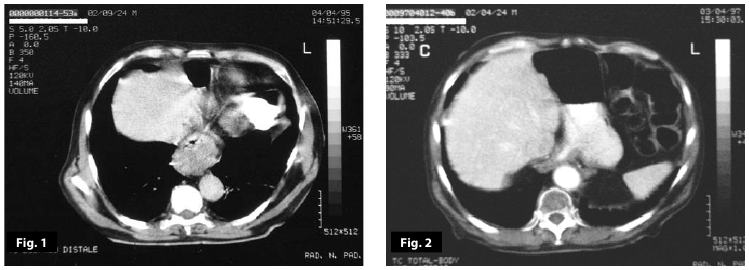

Figure1

Figure1-2

Figure1-2-3-4